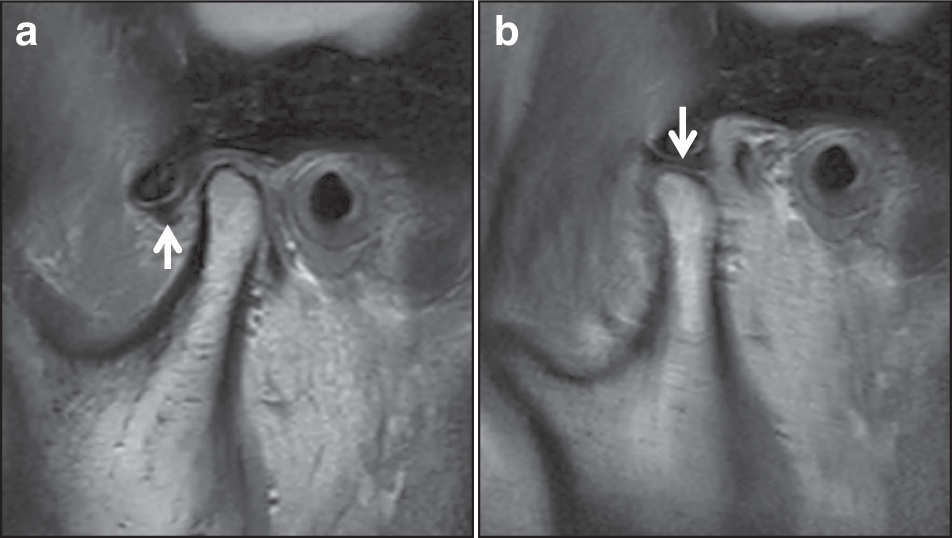

MRI PDWI imaging of anterior disc displacement with reduction, (a): in closed mouth position, (b): in open mouth position